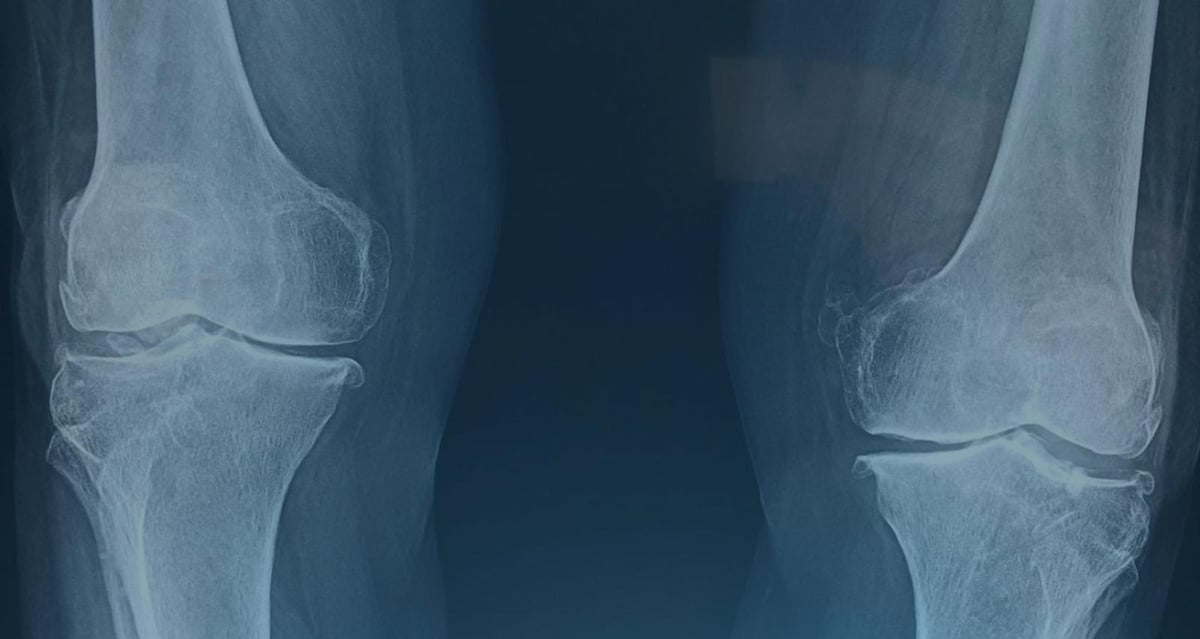

X-rays

X-rays are the most important and common tool used to diagnose osteoarthritis. This imaging technique allows doctors to see the state of the bones and the joint space. An X-ray can reveal two key signs of OA:

Narrowing of the Joint Space: As cartilage wears away, the space between the bones in the joint decreases. An X-ray can show this narrowing, indicating the extent of cartilage loss.

Bone Spurs (Osteophytes): These small, bony growths can form on the edges of the bones as the joint attempts to compensate for the lost cartilage.

X-rays are also used to stage the severity of the disease and monitor its progression over time.